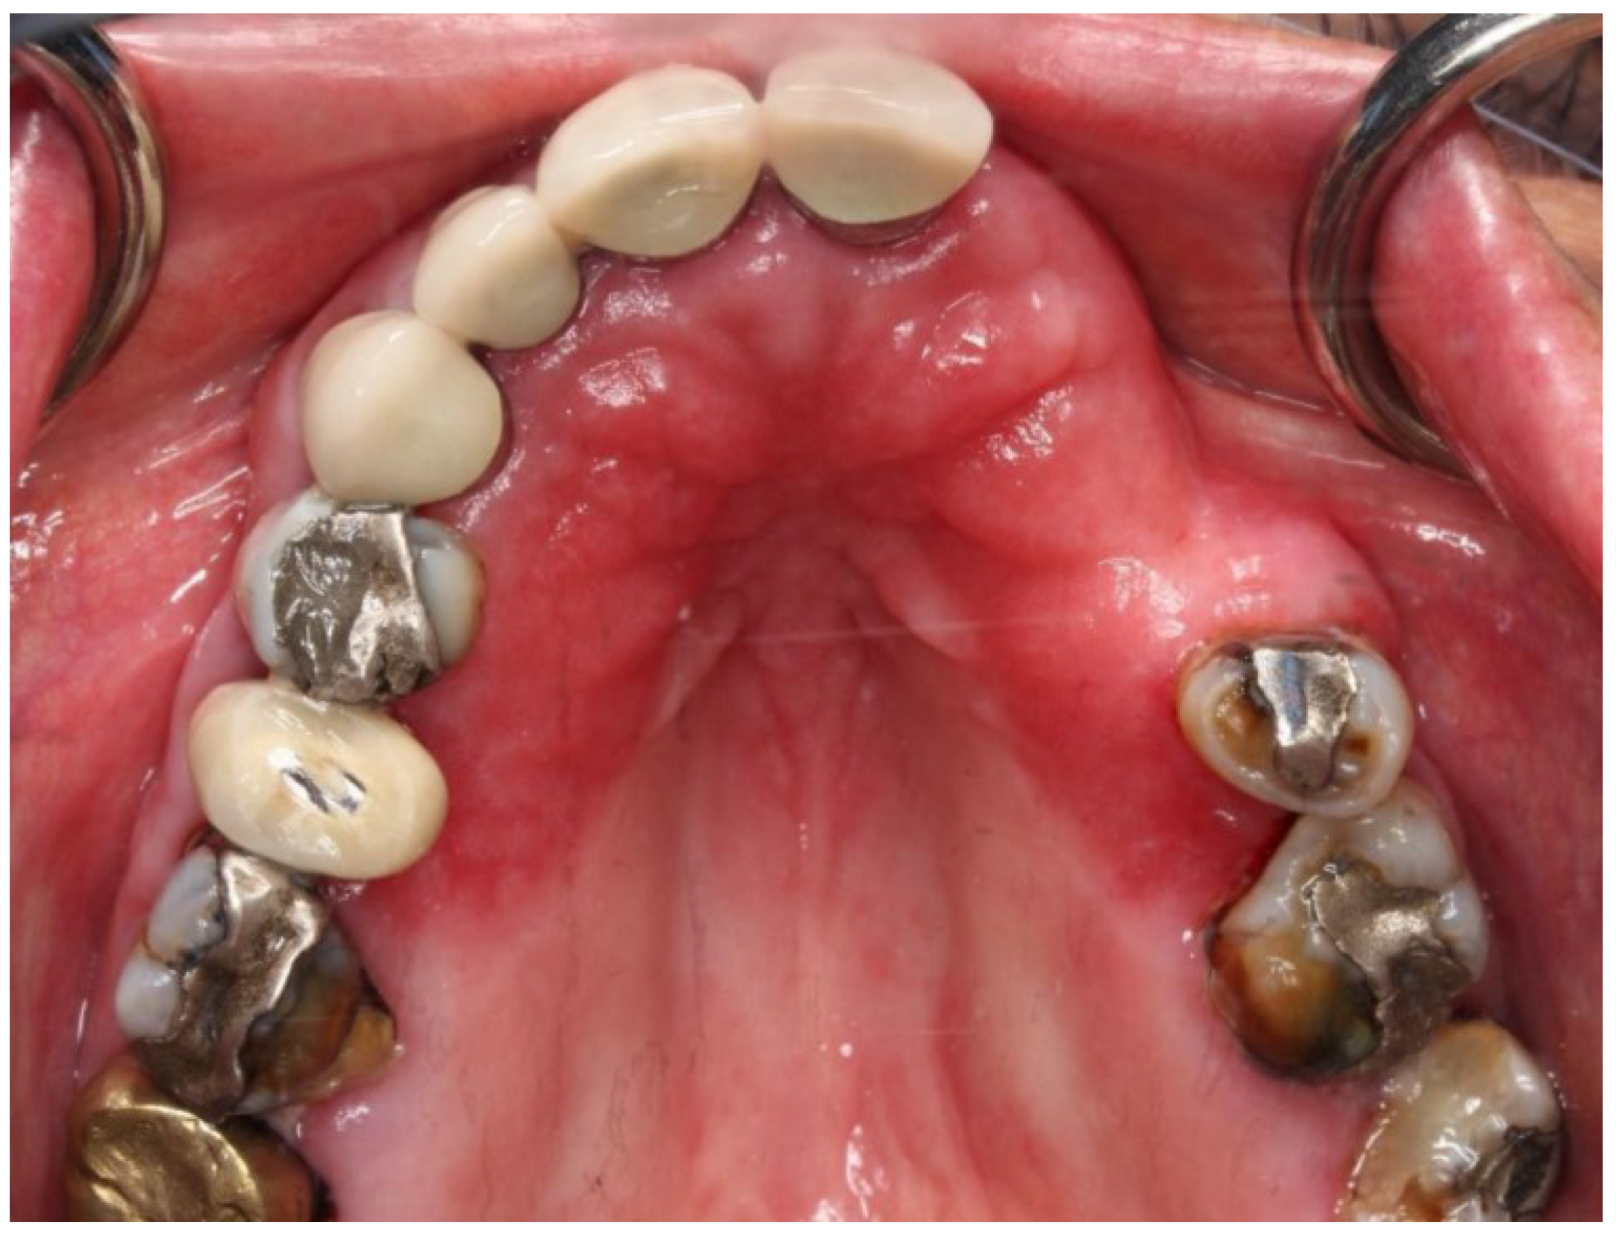

Denture Stomatitis

5. Pathogens in Denture Stomatitis